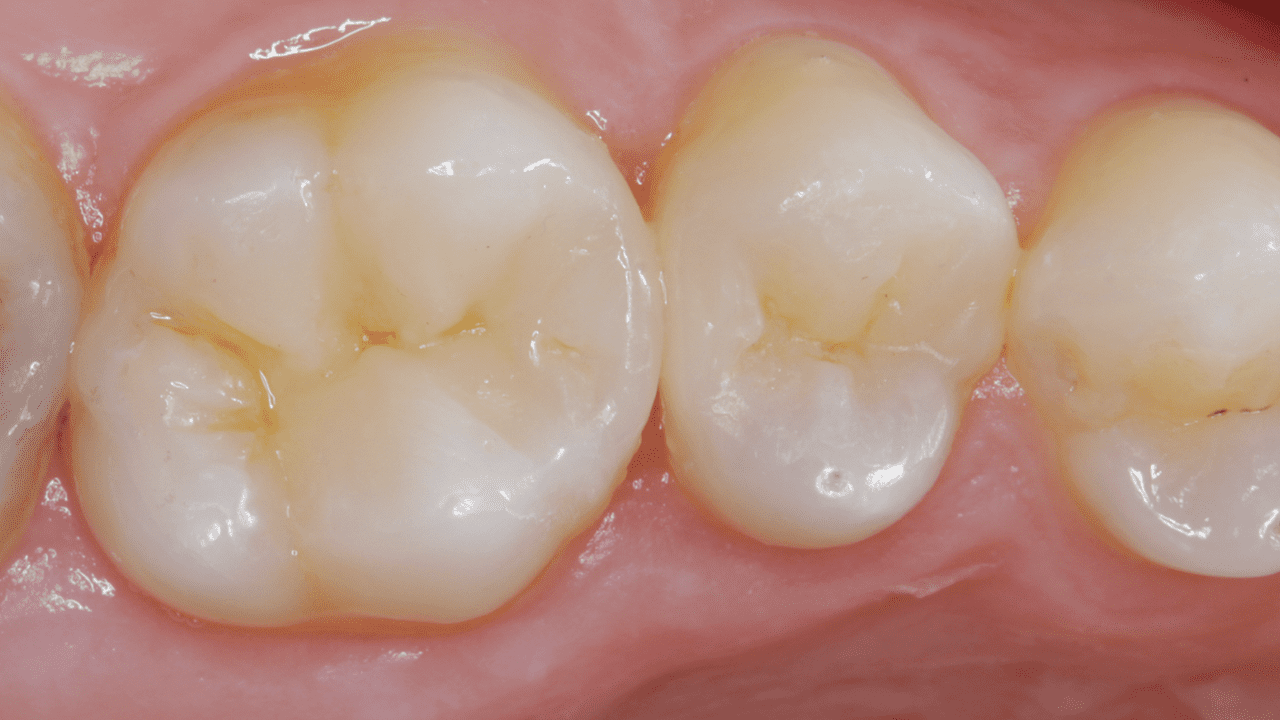

Получайте стабильные результаты с комплексным решением по II классу от Dentsply Sirona. Эта хорошо зарекомендовавшая себя методика позволяет решать ключевые проблемы процедуры благодаря инновационным продуктам для каждого отдельного этапа. В рамках решения для реставраций по II классу компания Dentsply Sirona предлагает продукты и методы, необходимые для того, чтобы успешно выполнить процедуру и обеспечить максимальную удовлетворенность пациентов.

Случай: Мужчина в возрасте 38 лет обратился с неудачной композитной реставрацией дисто-окклюзионной области нижнего моляра, выполненной по II классу. После клинической и рентгенографической диагностики была проведена анестезия, а затем удалена имеющаяся реставрация и проведена очистка кариозной области. Для проведения реставрации дисто-окклюзионной области по II классу было применено комплексное решение.

Вывод: Для снижения риска чувствительности в постоперационном периоде был применен метод селективного протравливания с использованием универсального адгезива. Для идеальной адаптации без зазоров использовался самовыравнивающийся композит объемного внесения SDR plus с низким полимеризационным стрессом. В дополнении, точный контур проксимальной полости и плотный контактный пункт обеспечила секционная матричная система Palodent V3.